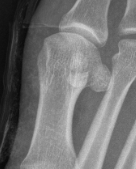

Imaging

Bilateral standing xray can help

Unclear if bipartite or stress fracture

Irregular borders suggest fracture rather than bipartite

CT demonstrates irregular borders consistent with fracture of tibial sesamoid